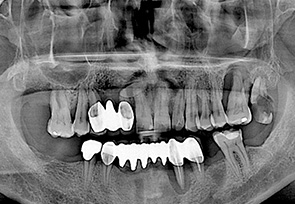

• before

• after